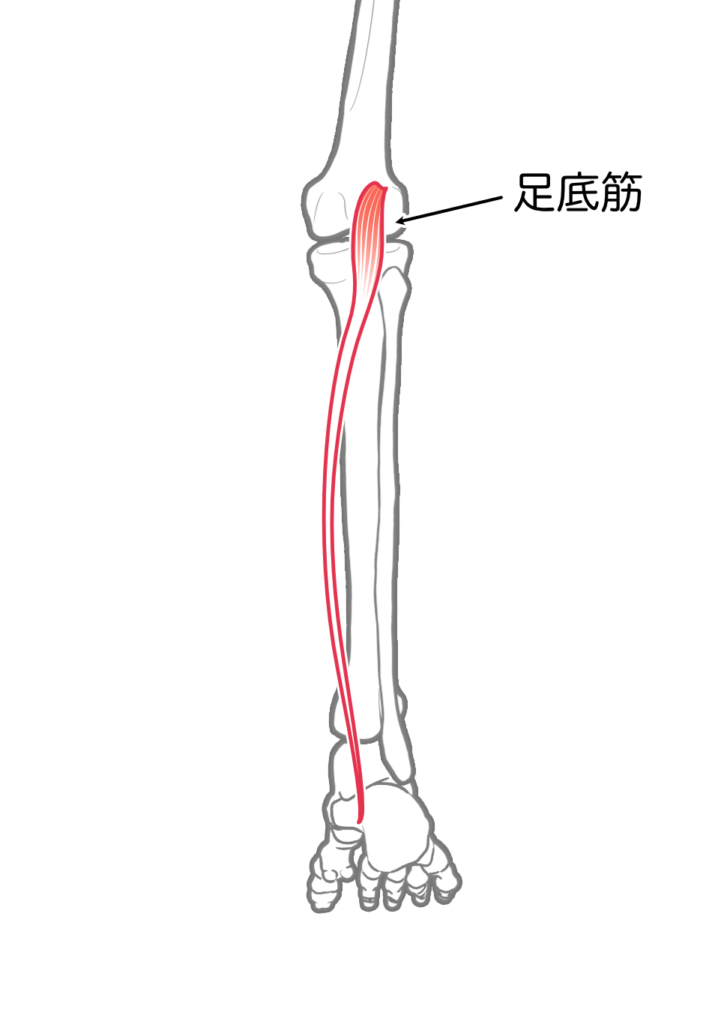

足底筋

| 起始 | 大腿骨膝窩面 |

| 停止 | アキレス腱に合流し 踵骨隆起 |

| 神経 | 脛骨神経L4-S1 |

| 作用 | 膝関節屈曲 |